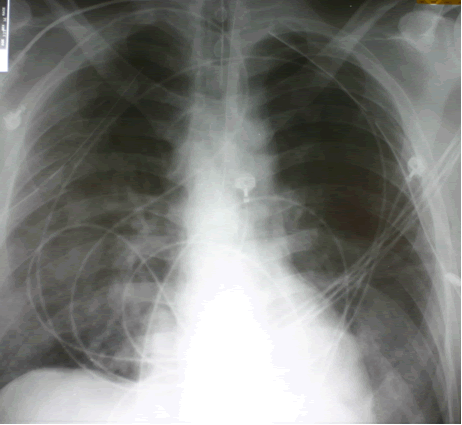

A 44 year old white male with 40 pack-year history of smoking was driving his motor cycle when a car struck him from the left side at approximately 40 mph. The patient lost consciousness at the scene, but upon arrival to trauma bay, he was alert and oriented. He complained of shortness of breath and pain in the left chest and left lower and upper extremity. The trauma team at the referring institution initiated advanced trauma life support pathway. He was found to have left femur, humerus, tibial-fibular and a complex pelvis fractures. The initial chest x-ray revealed a widened mediastinum (Figure 1), and a high-resolution contrast-enhanced computed tomography demonstrated proximal descending aortic rupture with hemomediastinum (Figure 2), left pulmonary contusion and a small left hemopneumothorax.